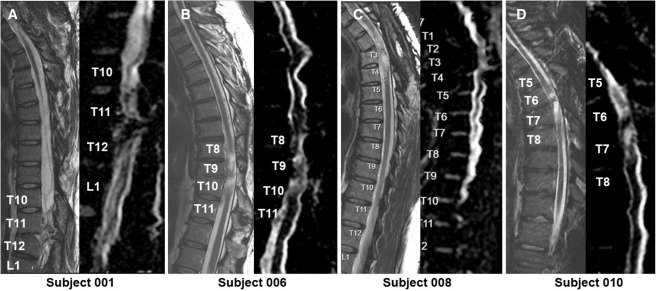

方法:每位受试者接受了每个注射点含有2×105个神经干细胞,通过定制的立体定向设备,双侧注入损伤部位周围的剩余组织及下方约一个节段的内侧白质区,整个过程由术中荧光透视成像指导完成。这一剂量基于临床前和早期临床研究确定为安全有效。(见图1)

为了评估神经干细胞(NSC)移植后的效果,研究人员在初次筛选、术后第4周和第12周进行了国际脊髓损伤神经分类标准检查(ISNCSCI),随后每六个月重复一次直至研究结束。初次ISNCSCI检查定义了最接近前端注射部位的神经水平尾部的第一个节段。(见图2)

- MRI成像显示所有患者均存在不同程度的局灶性脊髓软化症,但未发现新的并发症如脊髓或软组织水肿区域、增强或肿胀或积液等。(见图4)